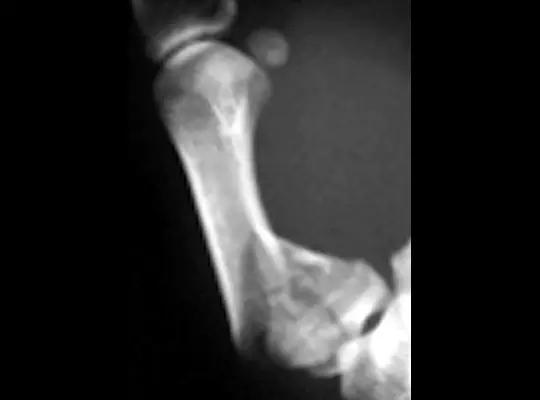

8. Aviator 骨折

飞行员骨折,是距骨颈骨折,在第一次世界大战期间被描述,是一种水平压力造成的骨折。

(来源:Dr. K. Lam Straight Talk: September 2015)